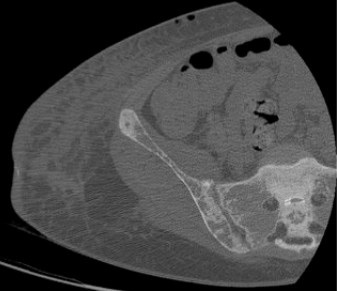

Рентгеновские снимки и визуализация болезни Педжета

Раздел: Мудрость в объективе